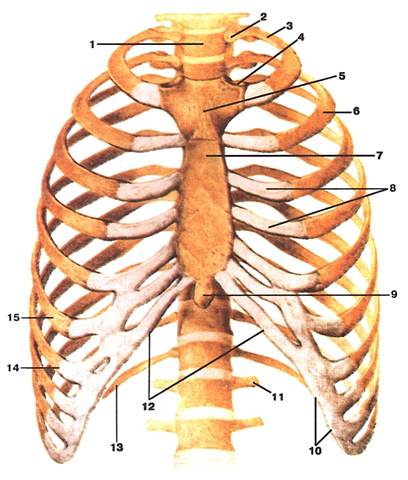

Малюнок А. 1 – Thorax. Вигляд спереду:

1 -vertebra thoracica (Thl); 2 -caput costae primae; 3 -costa prima; 4 -incisura clavicularis sterni; 5 -manubrium sterni; 6 -costa II; 7 -corpus sterni; 8 -cartilagines costales; 9 -processus xiphoideus; 10 -arcus costalis; 11 -processus costalis vertebrae lumbalis (LI); 12 -angulus infrasternalis; 13 -costa XII; 14 -costa VII; 15 -costa VI